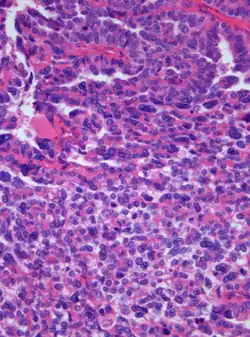

| Photomicrograph of hematoxylin-eosin stained section of a choroid plexus carcinoma (grade III WHO) at 400x magnification | |

A choroid plexus carcinoma (WHO grade III) is a type of choroid plexus tumor[1] that affects the choroid plexus of the brain. It is considered the worst of the three grades of chord plexus tumors, having a much poorer prognosis than choroid atypical plexus papilloma (WHO grade II) and choroid plexus papilloma (WHO grade I).[2] The disease creates lesions in the brain and increases cerebrospinal fluid volume, resulting in hydrocephalus.[3]